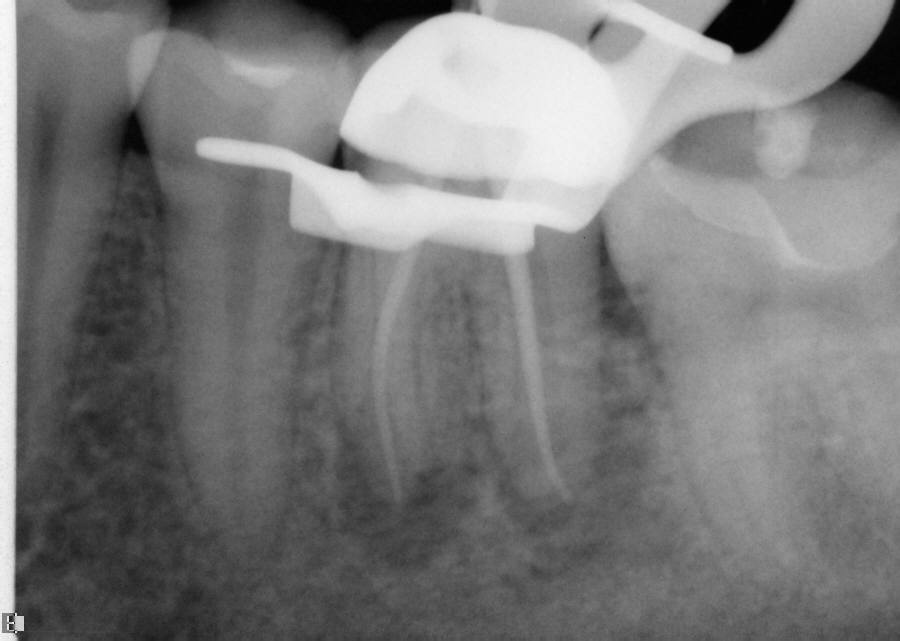

The question remains: how often should clinicians use apex locators, and are they really necessary? Because studies have shown them to be up to 96% accurate,8 it stands to reason that they could be used in every case possible. In some instances, the apex cannot even be seen radiographically. In these cases, using an apex locator is imperative to finding the true working length of the canals. The question remains: how often should clinicians use apex locators, and are they really necessary? Because studies have shown them to be up to 96% accurate,8 it stands to reason that they could be used in every case possible. In some instances, the apex cannot even be seen radiographically. In these cases, using an apex locator is imperative to finding the true working length of the canals. Figure 10 and Figure 11 through Figure 14 demonstrate two such cases; they likely would not have been successfully completed without the use of an apex locator. Even the final PA (Figure 14) does not clearly depict where the canals end.

Working films or radiographs, however, should not be completely eliminated from the clinician’s armamentarium. While practitioners may legally only be required to depict a preoperative and postoperative radiograph, from an endodontic point of view at least one working radiograph should always be taken. This does not mean that a master file radiograph has to be taken; however, it is prudent to take one in cases in which the anatomy is challenging, and the author recommends always taking a master cone radiograph (Figure 11 through Figure 14).

The master cone PA is the last indicator clinicians have in assessing whether or not their working lengths were truly accurate. This radiograph is crucial in affording the practitioner the opportunity to make adjustments to properly complete the procedure to the desirable lengths. An example is presented in Figure 15 through Figure 18. Figure 16 and Figure 17 show a master cone PA that demonstrates two of four canals to proper length. After adjusting the length of the other two master cones, the clinician was able to correct the lengths to produce a more appropriate result, as seen in Figure 18.

Fig 12. Working PA depicting arduous mesial bends and two mesial canals.

Figure 12